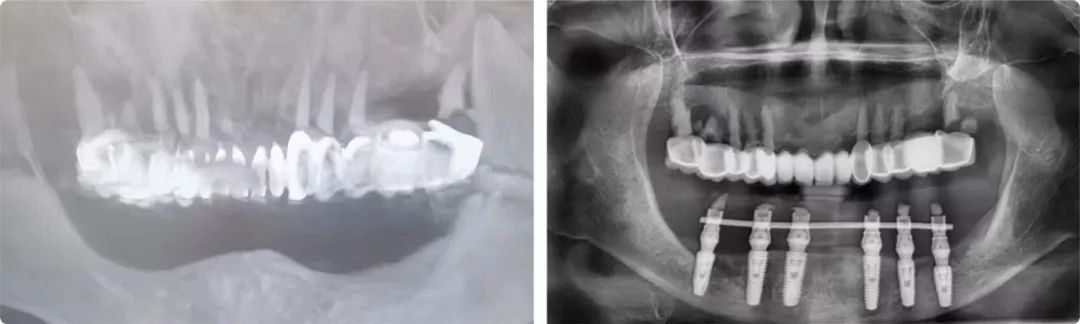

“患者牙槽骨的垂直高度太低,牙槽嵴高度不足9毫米,直接种植会伤及神经,首选方案是先做骨增量手术再种植,但她的情况根本做不了骨增量,只能选择高风险的第二方案:先行双侧下颌神经游离术,通过手术把左右两侧的下颌神经拨到安全位置,再做种植。”

患者术前术后检查报告

老人和家属非常信任姜辰,接受了这个方案。术中植入了6枚植体,术后即刻修复完成戴牙,老人的咀嚼功能当天恢复。